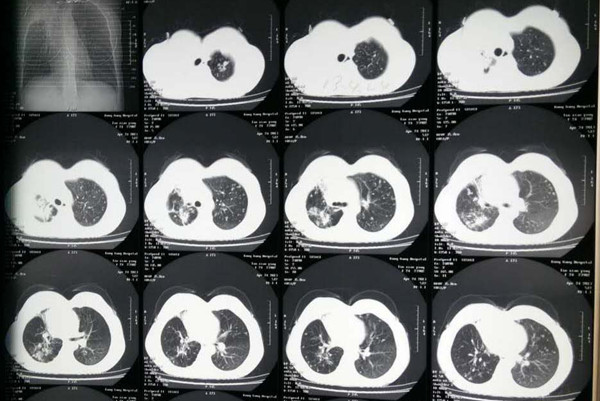

肺结核耐药是肺结核治疗中常见的一个情况,它是指肺结核患者在治疗中对药物的敏感性下降甚至消失,致使药物对肺结核疗效降低或无效,最后产生耐药现象,目前临床上根据肺结核病人是否接受过抗结核药物治疗,可分为原发性耐药、获得性耐药。那么出现这种耐药现象,大家就非常关心肺结核耐药能治好吗?